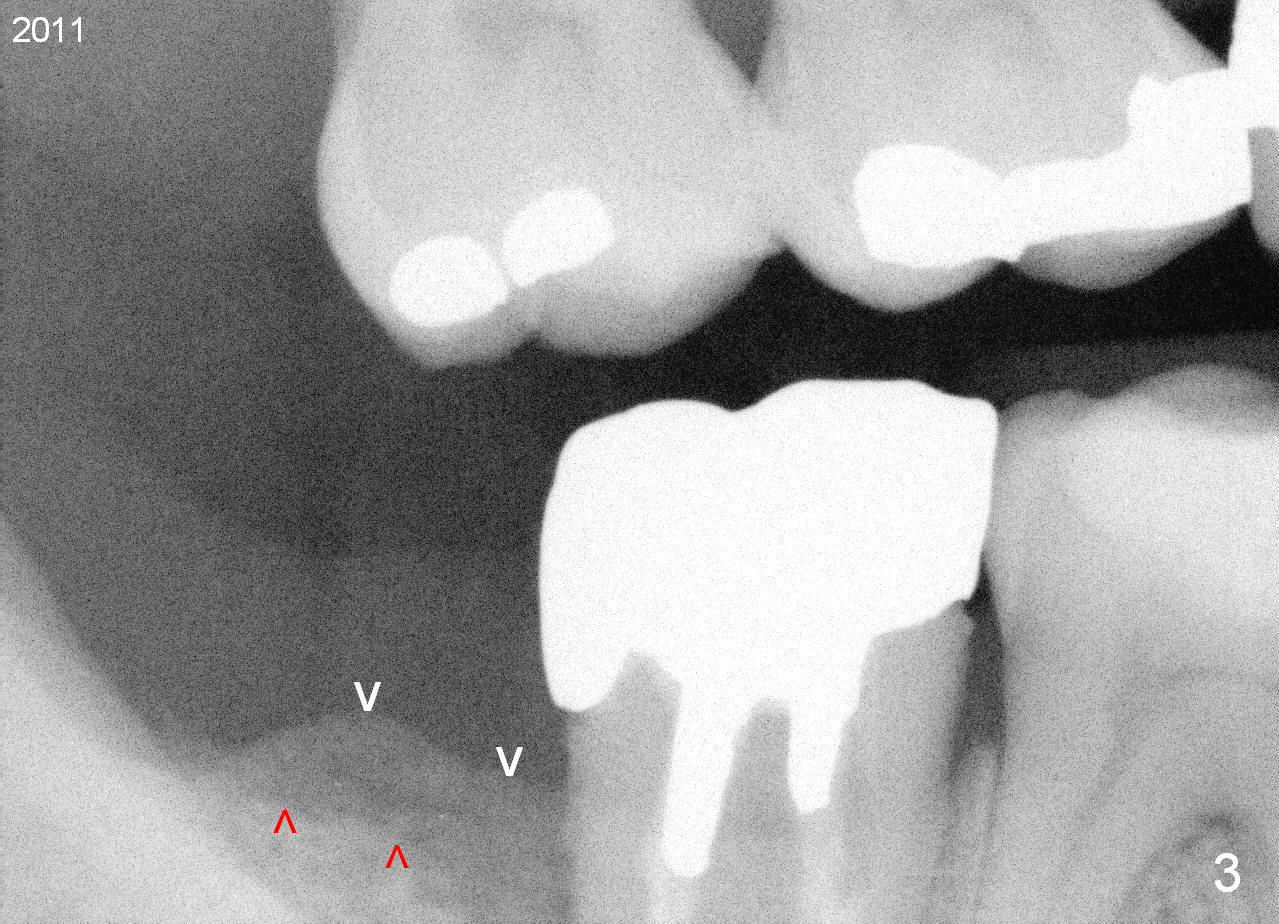

A 44-year-old man has had an asymptomatic distal defect of the tooth #31 for 8 years (Fig.1-5).  Recently there is an acute episode of swelling and pain.  A fistula develops mesiobucally.  Panoramic X-ray films tend to show that the distal defect is deep (Fig.2,5; yellow dashed line: upper border of the Inferior Alveolar Canal).  In addition, the distal defect may be not even buccolingually, as indicated by white and red arrowheads in Fig.3,4.  Following placement of a 6.9x10 mm bone-level implant, a 7.8x4 (4.5) mm cemented abutment is inserted for try in (Fig.6).  When it is fit, it is removed and a cover screw is temporarily placed.  A piece of Osteotape (~10x4 mm) is placed distobuccally or distolingually (depending upon which wall is lower).  A small amount of bone graft is packed between the most coronal portion of the implant and the Osteotape.  The cover screw is then removed and the abutment is re-inserted and tightened by hand.  An immediate provisional is fabricated with well-trimmed margin.  Reline is done if necessary for securely holding bone graft in place.  A new PA is to be taken prior to surgery to determine the extent of the lesion.  Photos are taken to show the mesiobuccal fistula.  Return to Lower Molar Immediate Implant Xin Wei, DDS, PhD, MS 1st edition 04/12/2015, last revision 05/25/2018